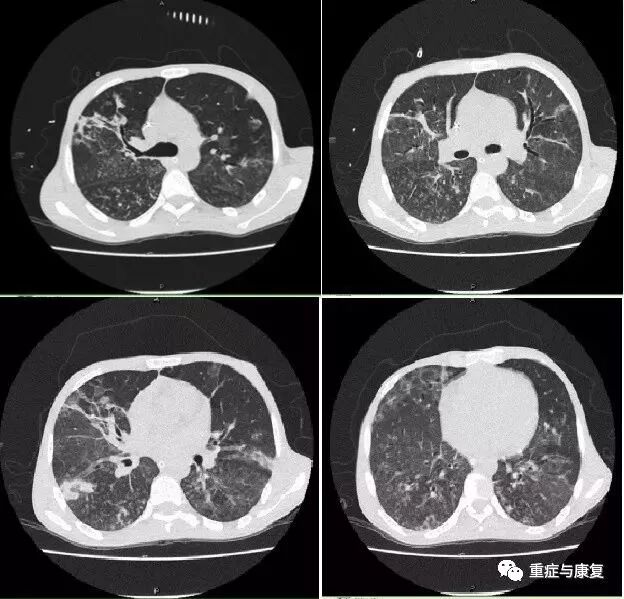

CT平扫(06-05):双肺广泛实变,考虑炎症;.双侧胸腔少量积液;心包少量积液;肝脾肿大;脾脏密度不均匀(图1-3)。

图1-3 胸部CT(2015-6-5)